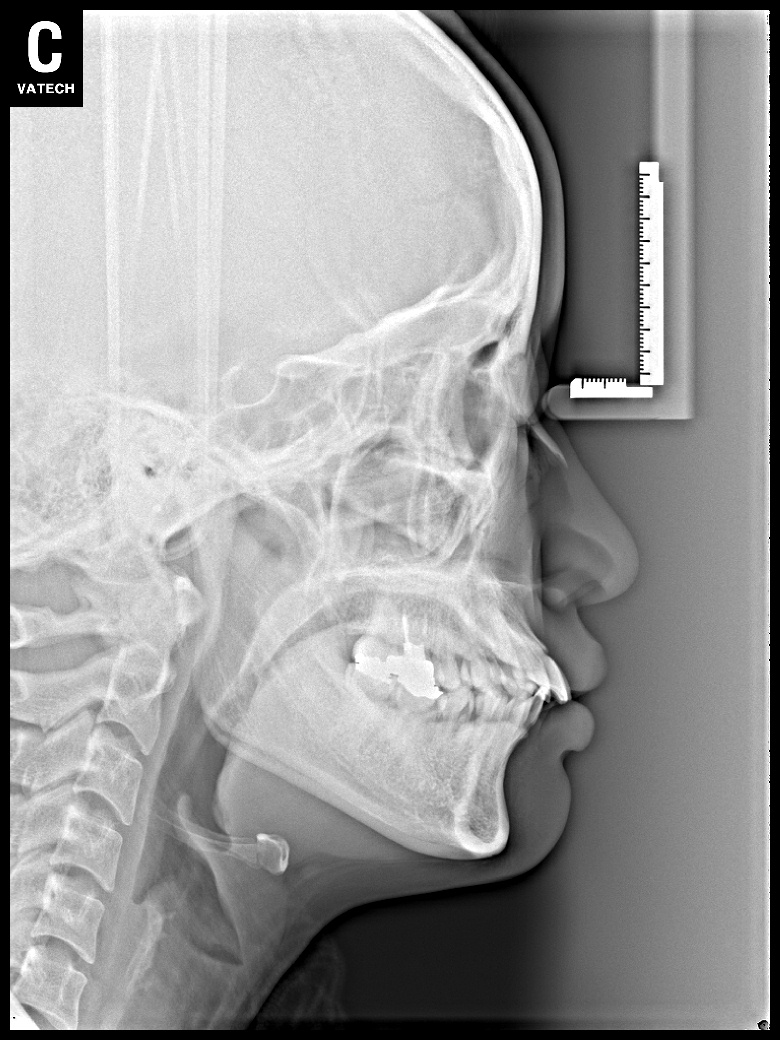

치료 전 사진입니다.